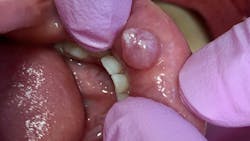

Patient: 6-year-old male

- 7 mm-plus soft, exophytic, dome-like lesion

- Normal lip color

- Fluid-filled with a slightly red base

- No pain, but patient was having a hard time eating due to position and size of lesion

- Patient had habit of biting his lip